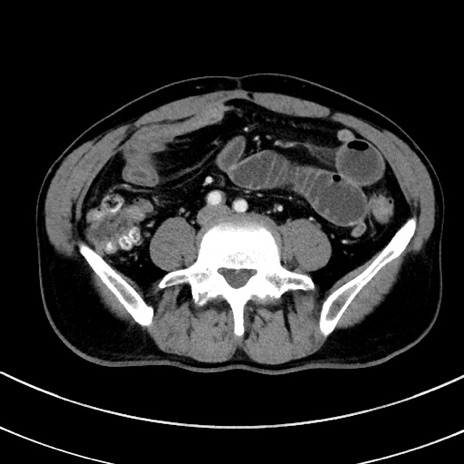

症例8(横断像)

【症例】 60歳代男性

【主訴】 黒色吐物

【現病歴】 4日前から嘔気自覚、2日前の朝食後にも嘔気あり、自分で手で嘔吐反射起こし嘔吐したところ血が混ざっていたため受診。

【既往歴】 5年前汎発性腹膜炎を伴う急性虫垂炎で手術、高血圧、前立腺肥大症、高脂血症

【身体所見】 腹部正中に手術癩痕あり 腹部平坦・軟圧痛なし膨満感あり

【データ】WBC 8400、CRP 4.54